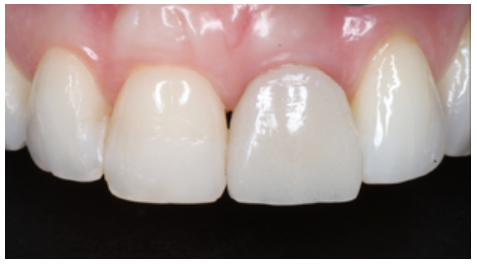

At 4 months, good stability of the OII was seen as a result of the proper osseointegration process. For the soft tissues, a decrease in the volume of the interdental papilla could be seen (Figure 21). Given the absence of signs and symptoms and the proper osseointegration of the OII, the subcritical profile was modified to improve the arrangement of the gingival soft tissue and promote recovery of this papilla (Figures 22 and 23).

At 6 months, proper arrangement of the soft tissues could be seen, with their stability over time due to their handling through the provisional prosthesis (Figure 24).